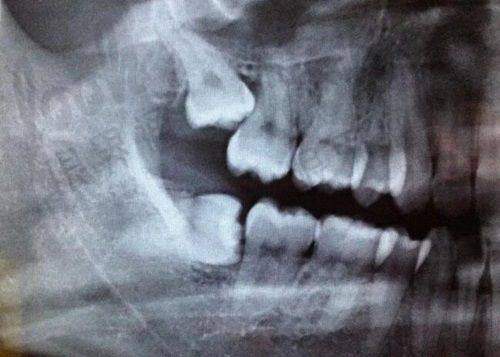

在石家庄找全博口腔特别方便——保利门诊守着体育南大街,万达门诊蹲在槐安路,北新门诊直接怼到军械学院西门对面。每家店都标配数字化CT机,拍片能看清牙根神经走向的那种,比某些国有医院的老设备还优质。重点来了:所有分院收费统一!在裕华店问的种植牙价格,跑到友谊门诊绝不会多收你一分钱。

技术院长甄翠欣透露过个小秘密:50岁以上选韩系够用,年轻人更推荐瑞士系,因为"要用大半辈子呢"。他们还创举了"种植牙模拟器",能预测20年后牙槽骨变化,这技术全省没几家有。

裕华区卫健局的工作人员私下透露:每次有口腔行业检查,都爱拿他们家当样板间。去年还承办了河北省数字化种植牙学术会,20多位骨干医生在手术室直播演示,这种实力在民营机构里属实罕见。